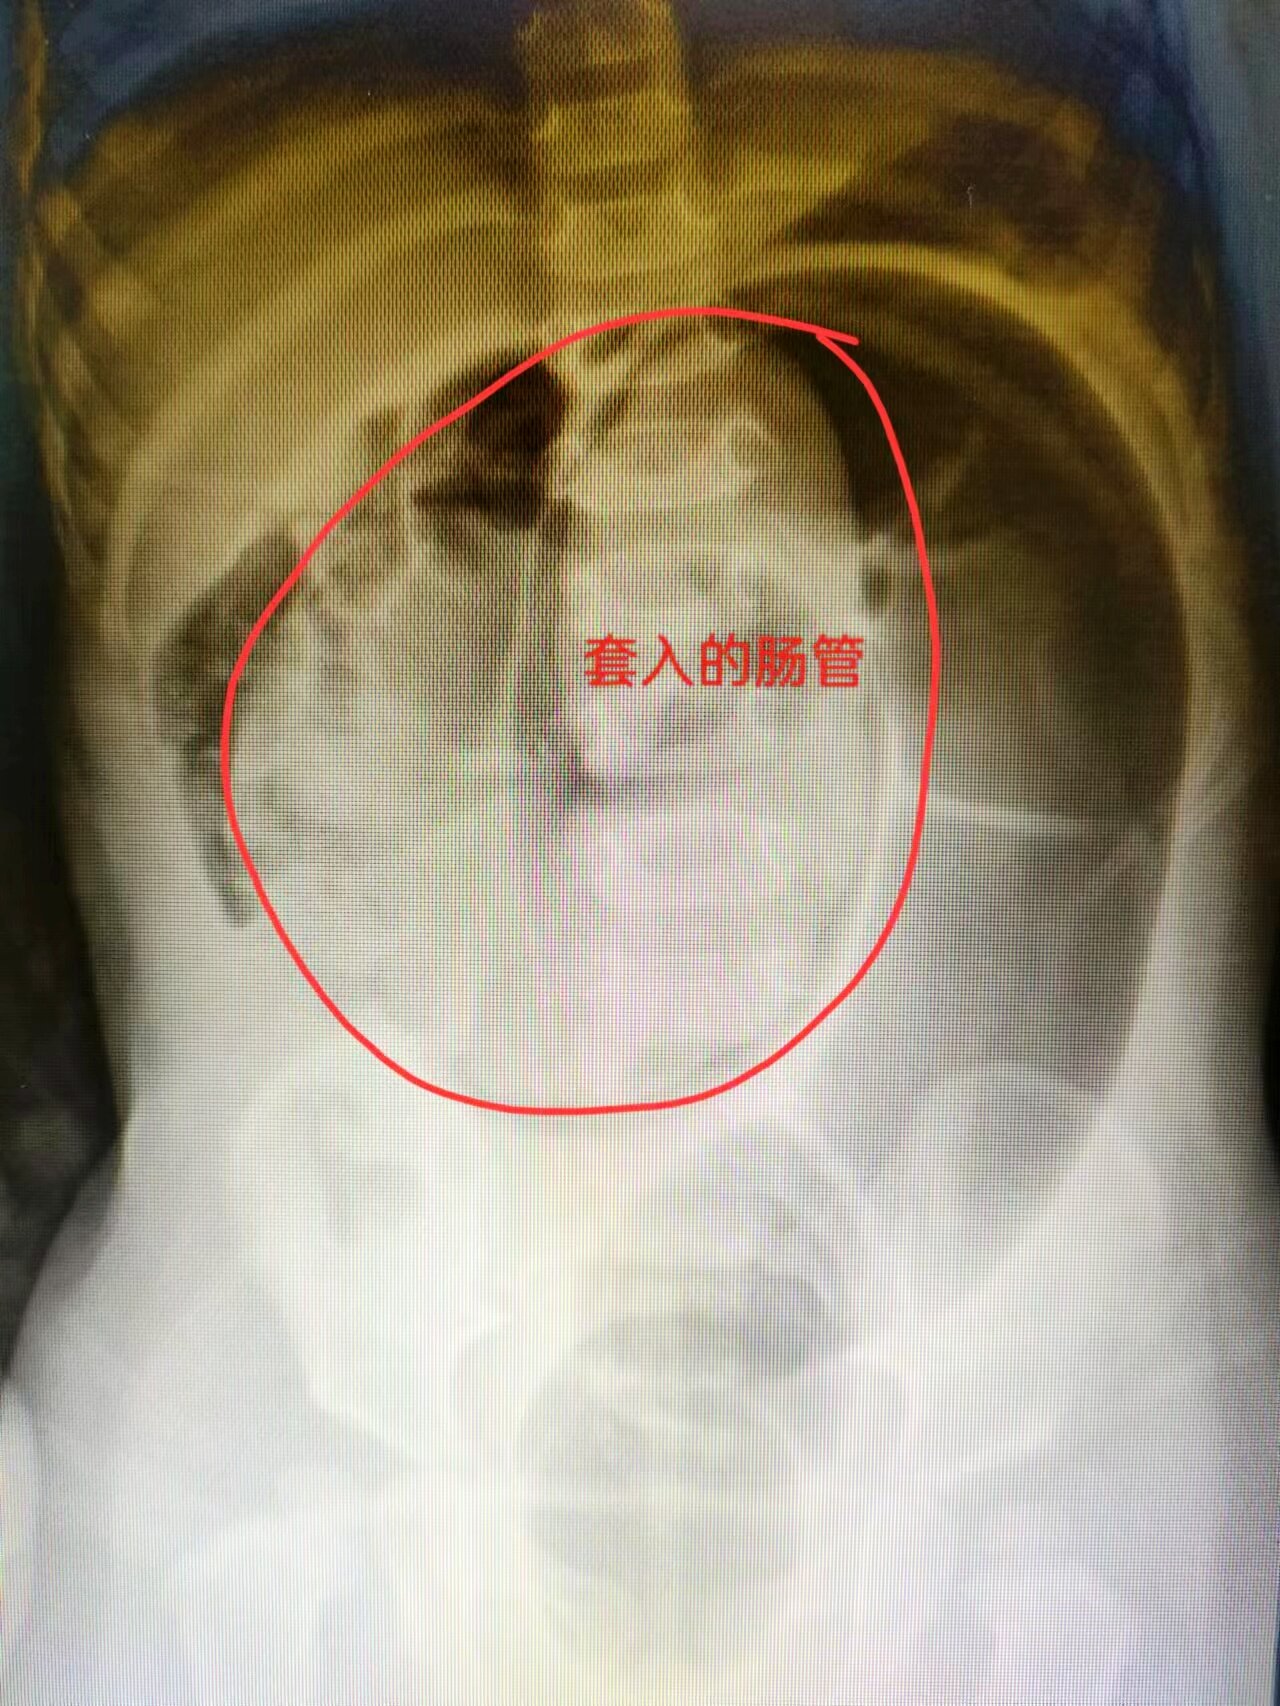

入院后,兒童重癥醫(yī)學(xué)科主治醫(yī)師張茜第一時間進(jìn)行擴(kuò)容,補液糾正休克、電解質(zhì)紊亂等以確?;純喊踩写才圆食瑱z查明確診斷為腸套疊、不排除腹內(nèi)疝,同時聯(lián)系小兒外科主任王松陽、主治醫(yī)師王艷平進(jìn)行會診,會診查體摸到患兒腹部包塊,行手法復(fù)位可由7cm大小縮小至3cm,進(jìn)一步復(fù)位困難。王松陽主任考慮患兒病情危重,且年齡小,建議盡量保守治療解決患兒腸套疊癥狀,并陪同患兒及家屬至放射科行空氣灌腸,預(yù)防空氣灌腸途中突發(fā)腸破裂、呼吸心跳驟停等意外。經(jīng)多次嘗試,腸套疊套頭可縮小但不能完全復(fù)位,且復(fù)位過程中患兒多次排血便。